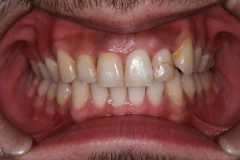

部分矯正とセラミックのハイブリット矯正にて治療例

上顎の前歯の部分矯正とセラミックを3本にて治療を行っています。